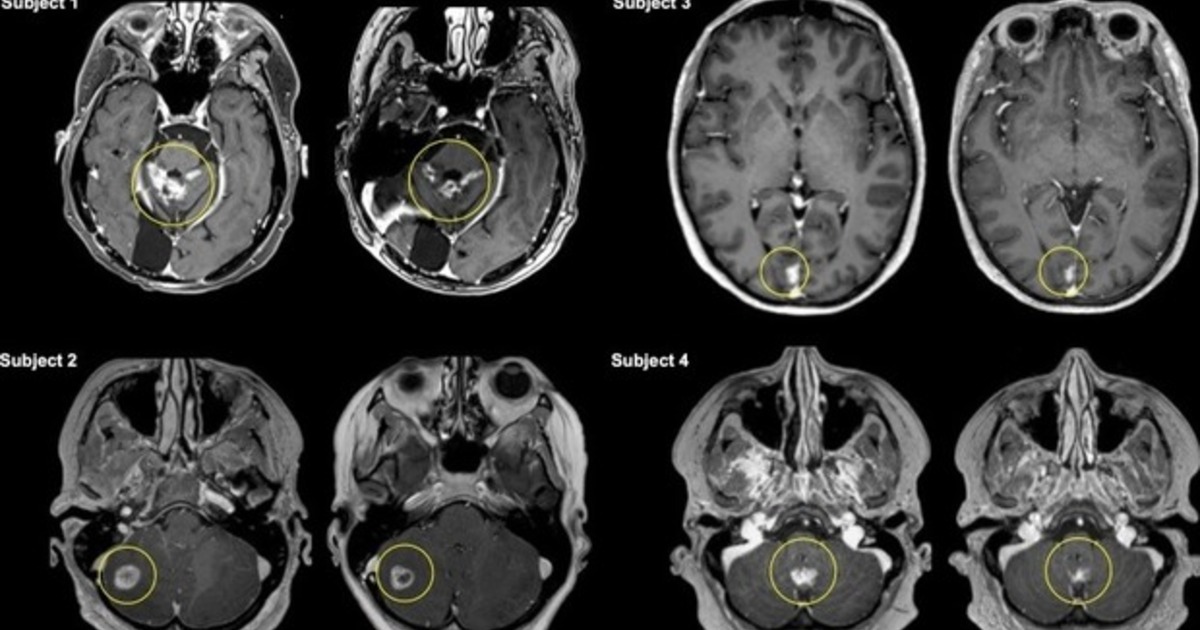

Канадские специалисты во главе с Ниром Липсманом из Университета Торонто впервые провели подобное исследование на людях. В кровь четырёх отобранных для эксперимента пациенток с раком груди, у которых уже были метастазы в мозге, был введён препарат Трастузумаб. Вместе с действующим веществом были введены пузырьки контрастного вещества, которые под воздействием управляемого ультразвука начинают вибрировать и открывают промежутки между эндотелиальными клетками, что позволяет проходить в них молекулам лекарства.

Источник пишет о том, что метод показал свою эффективность. У участниц был зафиксирован захват опухолью препарата, который оказался в два раза выше по сравнению со стандартными способами доставки лекарств. Отмечается, что размер опухоли у всех участниц за три месяца терапии и параллельных исследований уменьшился на 19%. Кроме этого, источник отмечает, что метод доставки лекарств через гематоэнцефалический барьер с помощью ультразвука полностью безопасен.